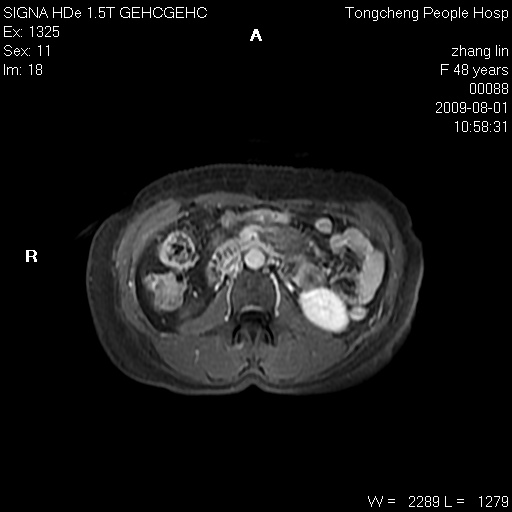

女,48岁。健康体检,彩超发现右肾占位性病变。平素健康。

临床诊断:右肾占位性病变,性质待定(囊肿?肿瘤?)。

上中腹部mr平扫+增强扫描,图像如下:

右肾上极见一类圆形病灶,t1wi呈等信号t2wi呈等高混杂信号,三期增强无强化,边界清---考虑囊肿出血。

同反相位均表现为等信号,病变无强化,考虑含蛋白的囊肿可能,弥散加权相或许有些帮助,

慢性胆囊炎